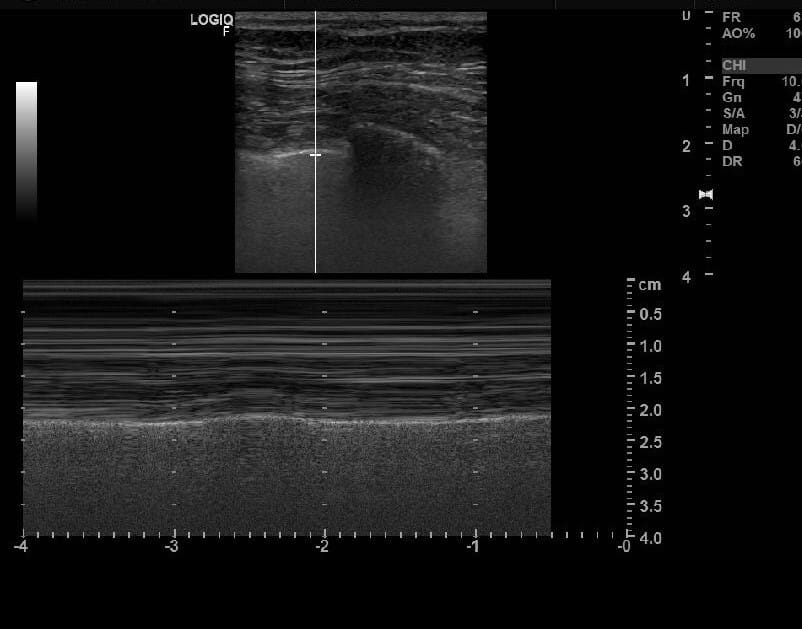

초음파 소견

응급 상황에서 빠르게 기흉을 진단하는 데 유용.

| 초음파 소견 |

| 🔵 폐활동 소실(Absent lung sliding): 정상적인 폐 움직임이 보이지 않음. |

| 🔵 바코드 사인(Barcode sign): M-mode에서 정상적인 파도 모양이 아닌 바코드 형태로 보임. |

| 🔵 폐 점프 사인(Lung point sign): 정상 폐와 기흉 부위의 경계를 확인 가능. |

기흉의 초음파 소견 (M-mode)

- Seashore sign : 정상 소견 , 파도 모양 (~~~)

- Barcode Sign : 비정상 소견, 바코드 모양 (===)